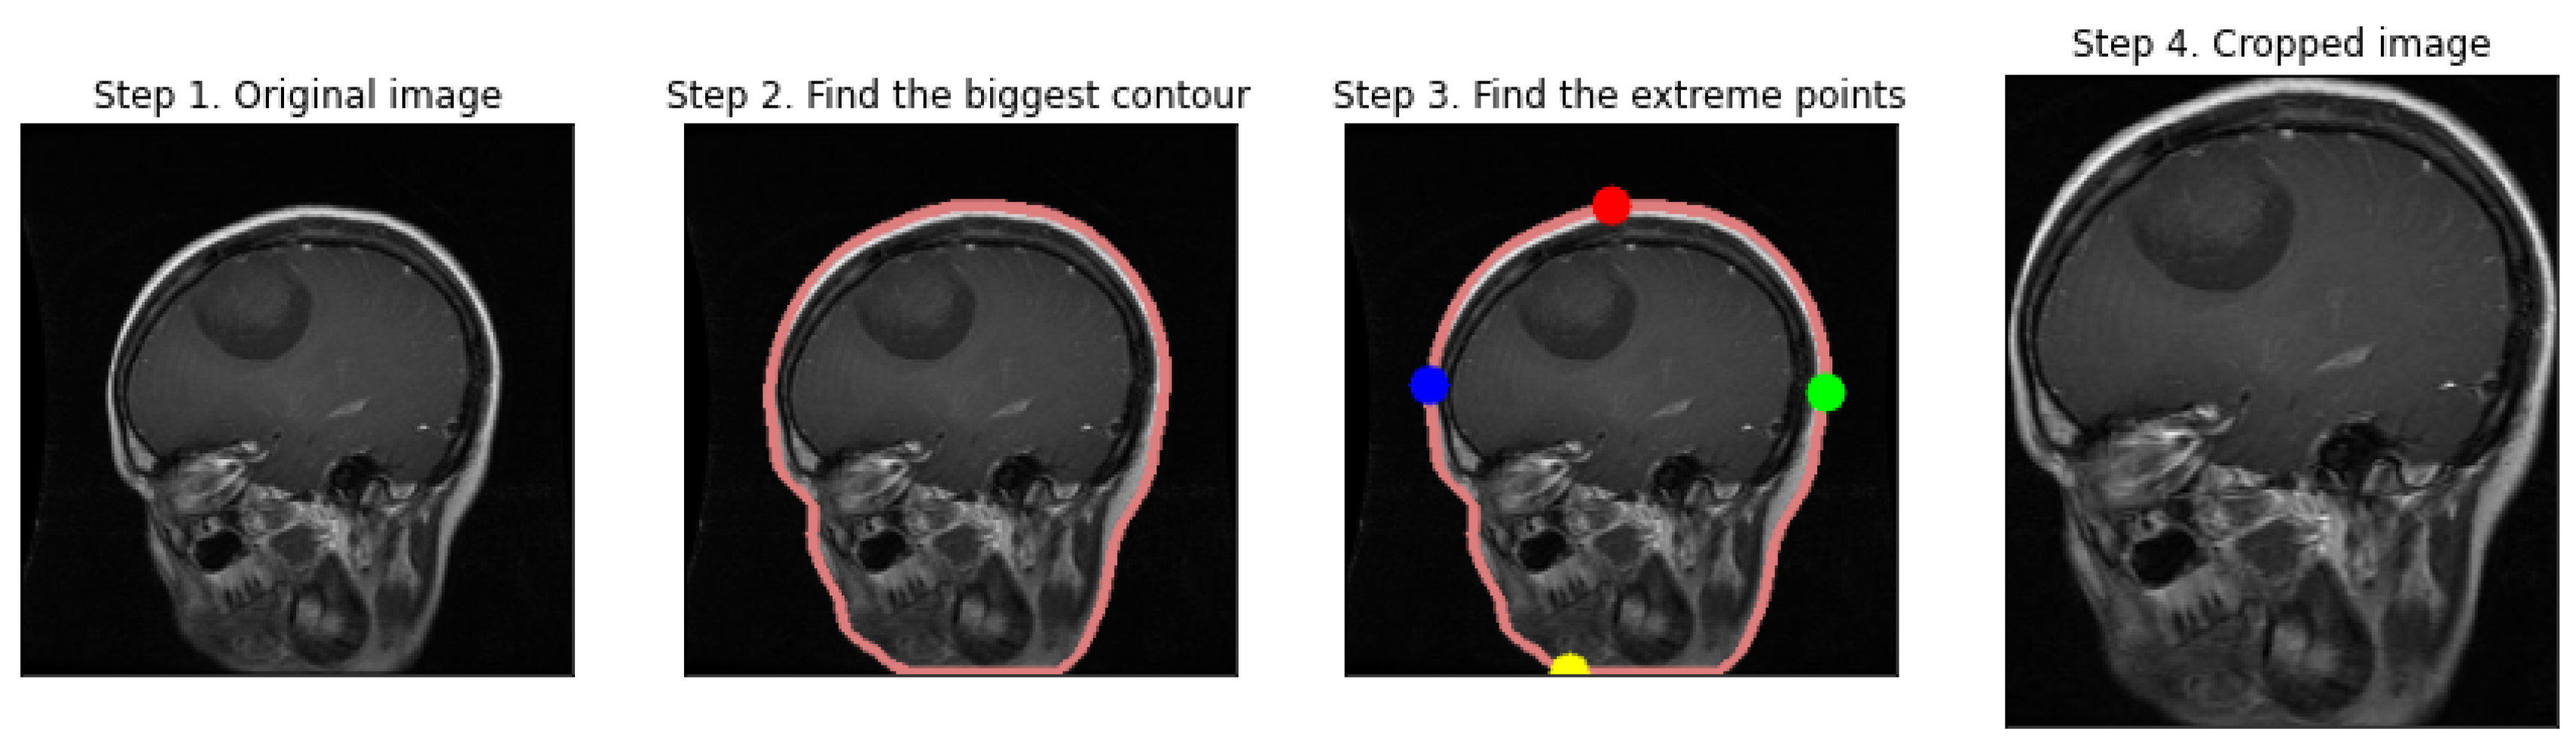

- Contour Detection and Selection: By applying contour detection, we identify the boundaries of all the objects in the binary image. We assume the largest contour to be the brain's boundary, a reasonable assumption in a typical MRI scan.

- Extreme Points and Cropping: Once the largest contour is identified, we verify its extreme points. These points represent the furthest pixels in the horizontal and vertical directions within the contour, which we employ to define a cropping boundary.

- Image Cropping: The image is cropped using the extreme points as vertices, with an optional padding added to ensure no part of the brain is excluded.

- Displaying the Process: We visualize the preprocessing steps, displaying the original image, the contour of the largest detected region, the extreme points, and finally, the cropped brain region.